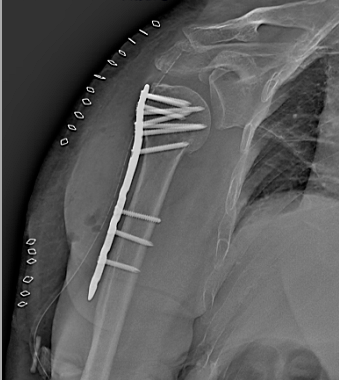

文章图片

术后X片

入院后 , 我院骨科主任胡医生立即组织科室成员展开讨论 , 结合患者身体情况、X线片、CT报告等资料 , 为患者制定了详细的治疗方案 。 在麻醉下由胡医生主刀 , 其他医生辅助配合 , 8月29日当天立即为患者实施“微创经皮钢板技术” , 一小时后手术圆满成功 。

术后 , 在医护人员的治疗、护理下 , 患者病情稳定 , 恢复良好 , 可自主活动 , 现已康复出院 。 手术的成功开展 , 为患者后期恢复提供了基础 , 也免除了患者以后身体活动受限的局限 , 家属对治疗效果非常满意 , 感激不尽 。